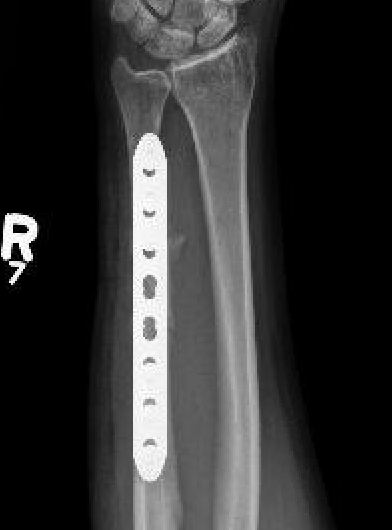

Compression plating

Ulna Intramedullary WireUlna Plating

AO foundation ulna plating

Ulna nonunion after plating